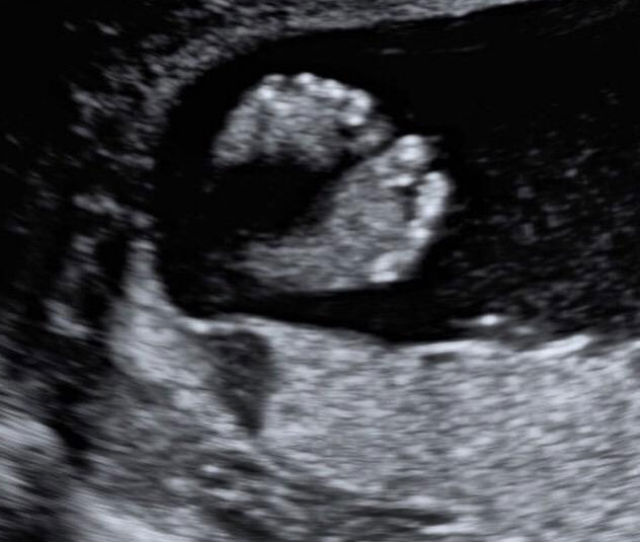

Anne Vyalitsyna urmează să devină mamă pentru prima oară și le-a arătat tuturor o ecografie cu bebelușul ei, încântată de faptul că cel mic este sănătos.